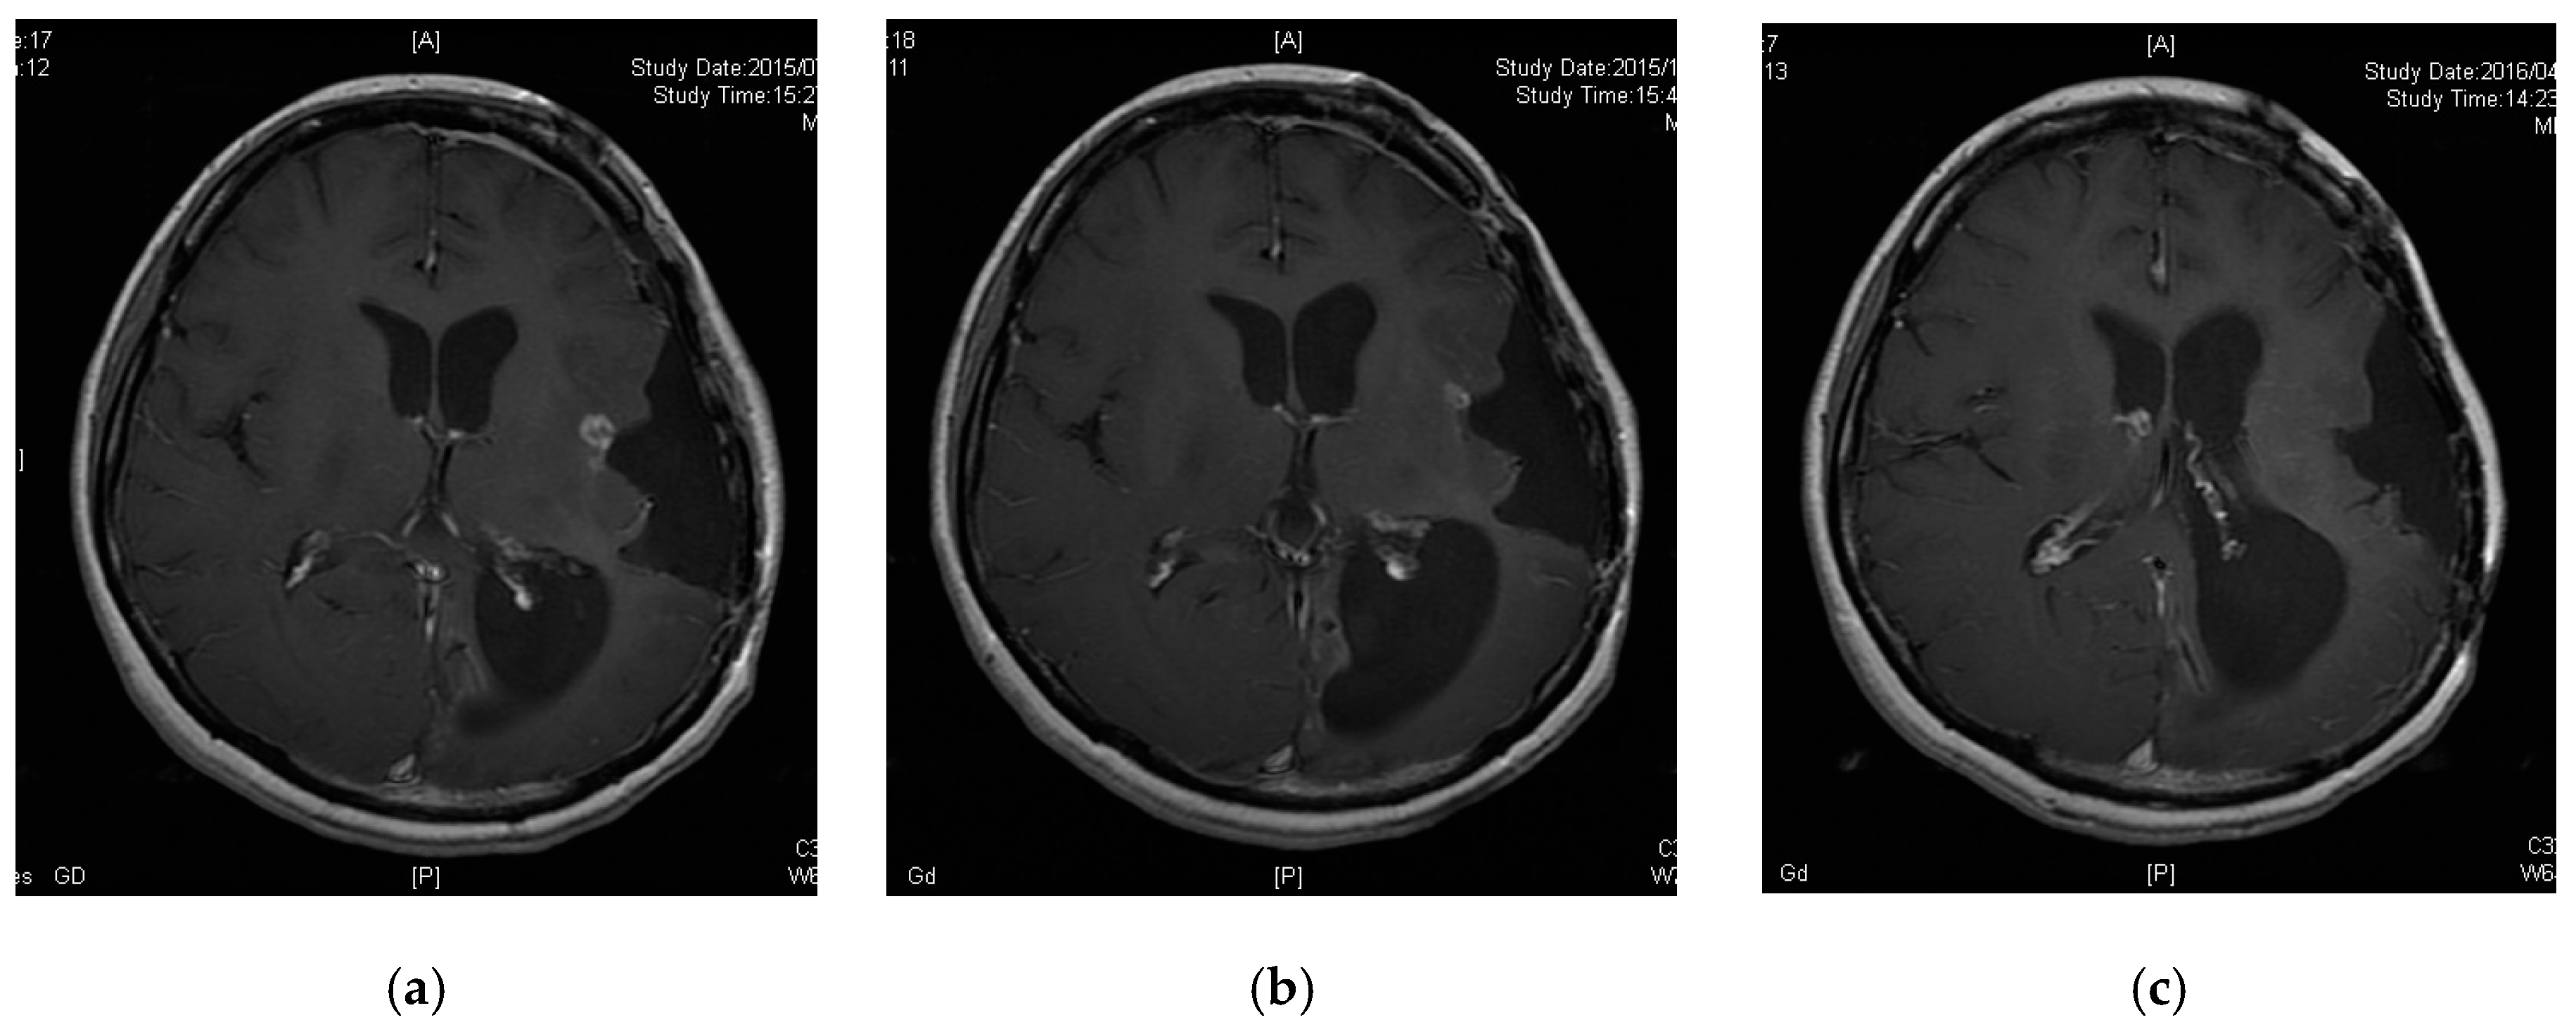

3.5. A Case of CR following Peptide Vaccination

Patient 6 was a 33-year-old female diagnosed with diffuse astrocytoma (grade 2) four years prior. Her tumor was enlarged and removed twice, followed by treatment with TMZ and radiation therapy for the preceding 12 months. The pathological diagnosis was anaplastic oligoastrocytoma (grade 3, MGMT unmethylated, IDH mutant and no 1p19q codeletion). However, her tumor recurred and could not be removed as it was located in a functional area (Figure 2a). She was thus enrolled in our study. Her tumor decreased in size three months after vaccine initiation and disappeared nine months after enrollment (Figure 2b,c). Thirty-eight months after the initiation of peptide vaccination, the patient remains free of tumor recurrence.

Figure 2.

Contrast-enhanced magnetic resonance images of Patient 6. (a) Tumor had recurred in a functional area; (b) tumor was decreased 3 months after enrollment; (c) tumor disappeared 9 months after enrollment.